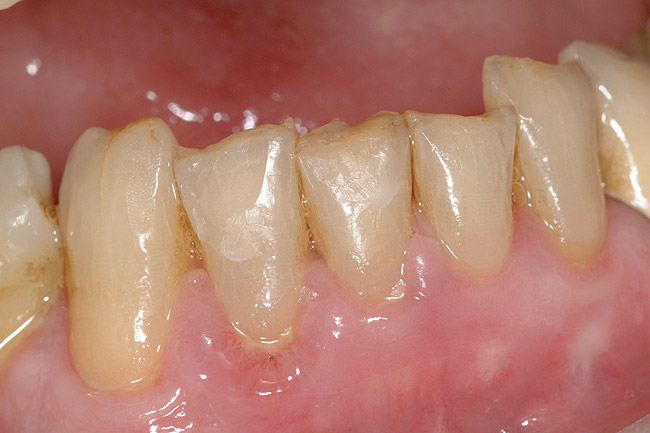

Figure  4  Possibly a combination of erosion and abrasion.

Figure 4

Characteristics of damage to tooth structures caused by acidity include wear on the occlusal surfaces of molars and a saucer shape on the cusps of molars (perimolysis).12 The erosion can vary from minor and subtle changes on the tooth surface, ie, loss of luster, a dull or matted look, to cupping on occlusal surfaces or incisal edges, which may extend to dentin. Usually, the erosive lesions demonstrate greater width than depth. When combined with abrasive forces or stresses, the tooth surface loss may occur at a faster rate (Figure 2, Figure 3, Figure 4 and Figure 5).

Abrasion is tooth surface loss due to friction caused by the abrasiveness of toothpaste and toothbrushes, which is necessary to remove biofilm and stains and to polish tooth surfaces. The rate of loss depends upon the degree of abrasivity, magnitude of force, contact time, and frequency of physical contact (Figure 6). Abrasives in toothpastes include silicates, alumina, calcium phosphate, and calcium carbonate. Manly showed non-significant changes caused by the toothbrush13 but that the hardness of the brush and the concentration of abrasive are important influences on wear caused by dentifrice abrasives and that the degree of influence depends on the abrasive.14-16 Toothpaste slurry abrasivity affects abrasion and tooth surface loss,17 and a larger amount of slurry can be produced with softer rather than stiffer toothbrushes. However, some research has not found a correlation between toothpaste and cervical lesions.18 Abrasive lesions have greater axial depth than the gingivo-occlusal distance and may possess sharp angles.